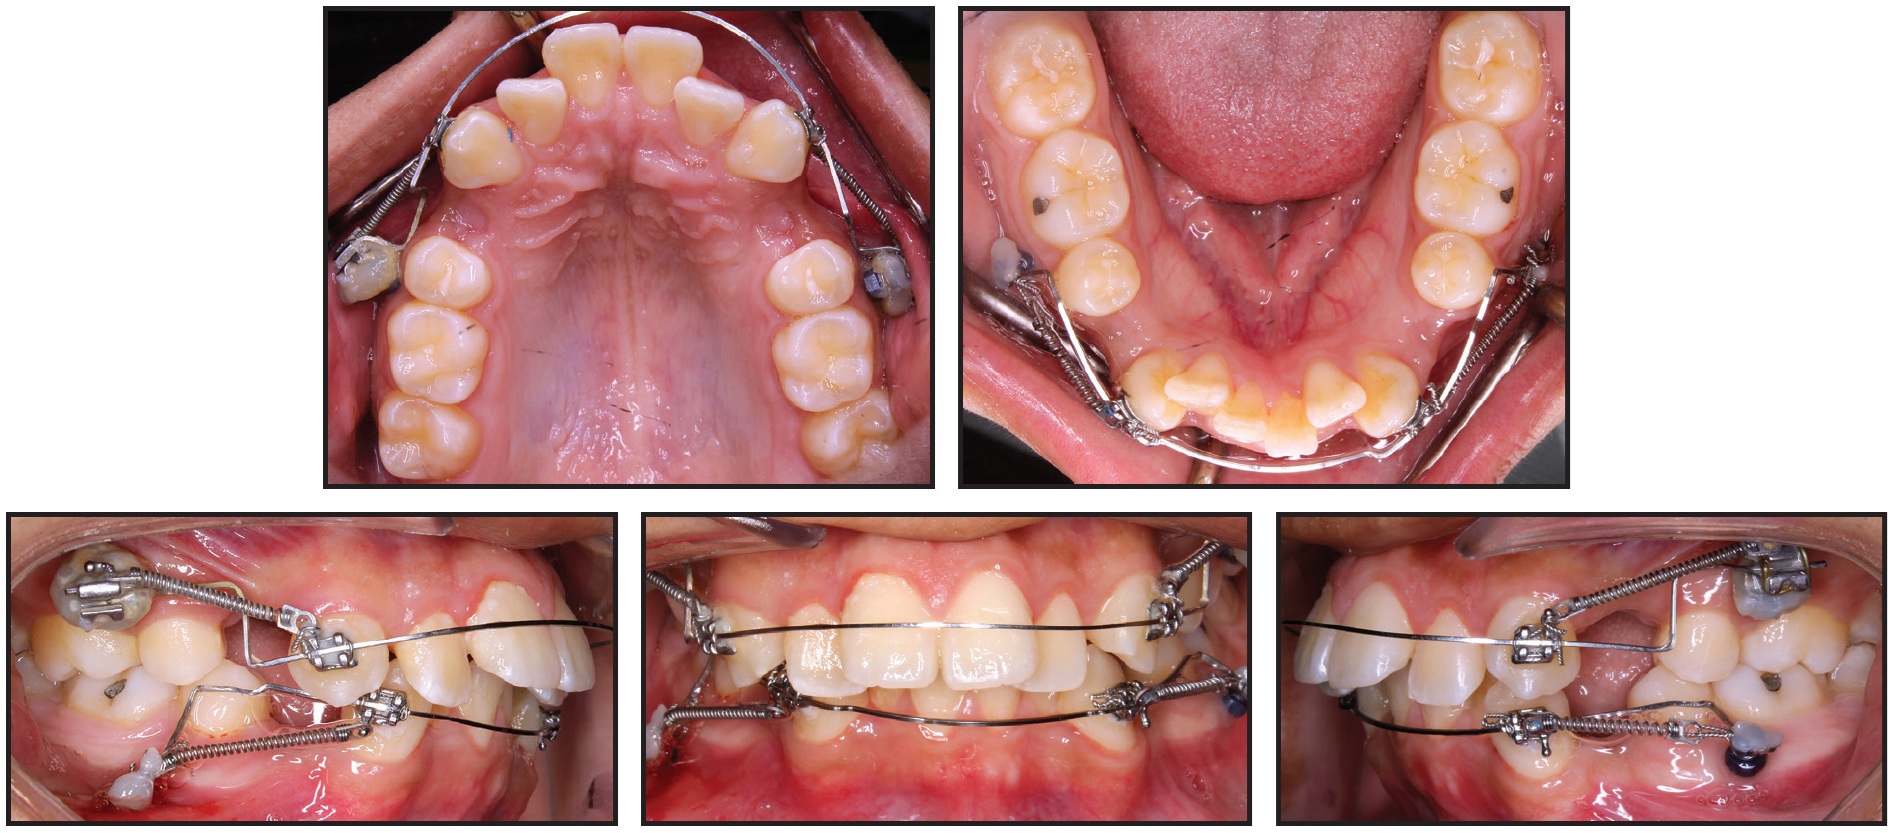

The patient was referred to his general dentist for extraction of the upper and lower first premolars. Four LOMAS* 1.5mm × 9mm, 022"/.028" slot mini-implants were placed in the maxilla, two on each side, in a vertical configuration between the first molar and second premolar. The mini-implants on each side were splinted together with a mesh of stainless steel ligature ties and composite resin. A molar tube was then bonded to each stabilized mini-implant structure to engage the base archwire (Fig. 3).

Fig. 3 Targeted mechanics for canine retraction: four mini-implants placed in maxilla and two in mandible, .022" preadjusted edgewise brackets bonded to upper and lower canines, .016" × .022" stainless steel archwires passively adapted to engage slots of canines and mini-implant brackets, and nickel titanium coil springs attached from canine brackets to mini-implants.

Two additional mini-implants were placed in the mandible, one on each side, between the first molar and second premolar.

Preadjusted .022" edgewise brackets** were bonded to the upper and lower canines, and .016" × .022" stainless steel archwires were passively adapted to engage the slots of the canine and mini-implant brackets. Canine retraction was initiated by attaching nickel titanium coil springs with 120-150g of force from the canines to the mini-implants. Six months later, some spontaneous alignment of the upper and lower incisors was observed as a result of the anterior space creation (Fig. 4). A progress panoramic radiograph indicated translation of the upper canines and lower left canine; the lower right canine was slightly tipped.

Fig. 4 After six months of canine retraction, incisor alignment spontaneously improved.

After 11 months of canine retraction, we noted additional spacing in the incisor regions and further spontaneous alignment of the upper and lower incisors, along with substantial movement of the left canines (Fig. 5). Some 3-4mm of space remained distal to the right canines.

Fig. 5 After 11 months of canine retraction, transpalatal arch soldered to upper canine bands and elastomeric chains attached from extension arms to mini-implants.

The maxillary mechanics were then modified for transverse control, with an .030" stainless steel transpalatal arch soldered to bands on the upper canines. Extension arms were soldered to the buccal surfaces of the bands so that the lines of force would pass close to the canine centers of resistance, and canine retraction was continued with elastomeric chains from the extension arms to the mini-implants. The previous mechanics were maintained in the mandibular arch.

Both upper canines and the lower left canine were fully retracted after 20 months of treatment. At this stage, both arches were bonded with .022" preadjusted edgewise brackets, and mini-implants were removed (Fig. 6).

Fig. 6 Both arches bonded with .022" preadjusted edgewise brackets, mini-implants removed, and leveling and alignment initiated after 20 months of treatment.